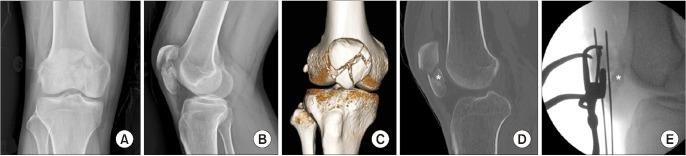

Treatment of comminuted patellar fractures accompanied by coronal split articular and inferior pole fragments is a challenge. To treat this difficult fracture, we perform articular fragment detachment and separate fixation for coronal split articular and inferior pole fragments. We aimed to evaluate the radiological and clinical outcomes of our technique in comminuted patellar fractures at least 1 year after surgery.

Between January 2019 and June 2022, 15 patients diagnosed with comminuted patellar fractures accompanied by coronal split articular and inferior pole fragments based on preoperative computed tomography underwent surgery using the articular detachment technique. The key point of this technique was anatomical reduction and subchondral fixation of the coronal split articular fragment to the superior main fragment after complete detachment of the coronal split fragment from the inferior pole. The remaining inferior pole was fixed using a separate construct. Postoperative articular gap, articular step-off, and complications, including resorption, reduction loss, and avascular necrosis of fixed articular fragments, were evaluated as radiological outcomes. Range of motion and the Lysholm scores were used to evaluate clinical outcomes.

Among the 15 patients, the coronal split articular fragments were fixed using Kirschner wires in 13 patients and headless screws in 2 patients. The inferior poles were fixed using separate vertical wiring in 13 patients and tension-band wiring in 2 patients. A postoperative articular gap was noted in 7 patients, with an average articular gap of 1.0 mm (range, 0.7-1.6 mm). No articular step-off was observed. Bone union and normal range of motion were achieved in all patients. On the 1-year postoperative lateral radiograph, resorption of the articular fracture site was seen in 5 patients. There was no loss of reduction or avascular necrosis of the coronal split articular fragments. The average postoperative Lysholm score at 1 year was 89.3 ± 4.1 (range, 82-95).

治疗伴有冠状面关节分裂和髌骨下极碎片的粉碎性髌骨骨折是一个挑战。为了治疗这种复杂的骨折,我们对冠状面关节分裂和髌骨下极碎片进行关节片游离和单独固定。我们旨在评估我们的技术在术后至少 1 年治疗粉碎性髌骨骨折的放射学和临床结果。

2019 年 1 月至 2022 年 6 月,根据术前 CT 诊断为伴有冠状面关节分裂和髌骨下极碎片的粉碎性髌骨骨折的 15 例患者采用关节游离技术进行手术。该技术的关键是在完全游离冠状面关节片与髌骨下极后,对冠状面关节片进行解剖复位和软骨下固定至主要上髌骨片。剩余的髌骨下极采用单独的固定方式。术后关节间隙、关节台阶和并发症(包括吸收、复位丢失和固定关节片的缺血性坏死)被评估为放射学结果。关节活动度和 Lysholm 评分用于评估临床结果。

在 15 例患者中,13 例采用克氏针固定冠状面关节片,2 例采用无头螺钉固定。13 例采用单独的垂直布线固定髌骨下极,2 例采用张力带布线固定。7 例患者术后出现关节间隙,平均关节间隙为 1.0mm(范围为 0.7-1.6mm)。未观察到关节台阶。所有患者均获得骨愈合和正常的关节活动度。在术后 1 年的侧位 X 线片上,5 例患者可见关节骨折部位吸收。冠状面关节片无复位丢失或缺血性坏死。术后 1 年平均 Lysholm 评分为 89.3±4.1(范围为 82-95)。